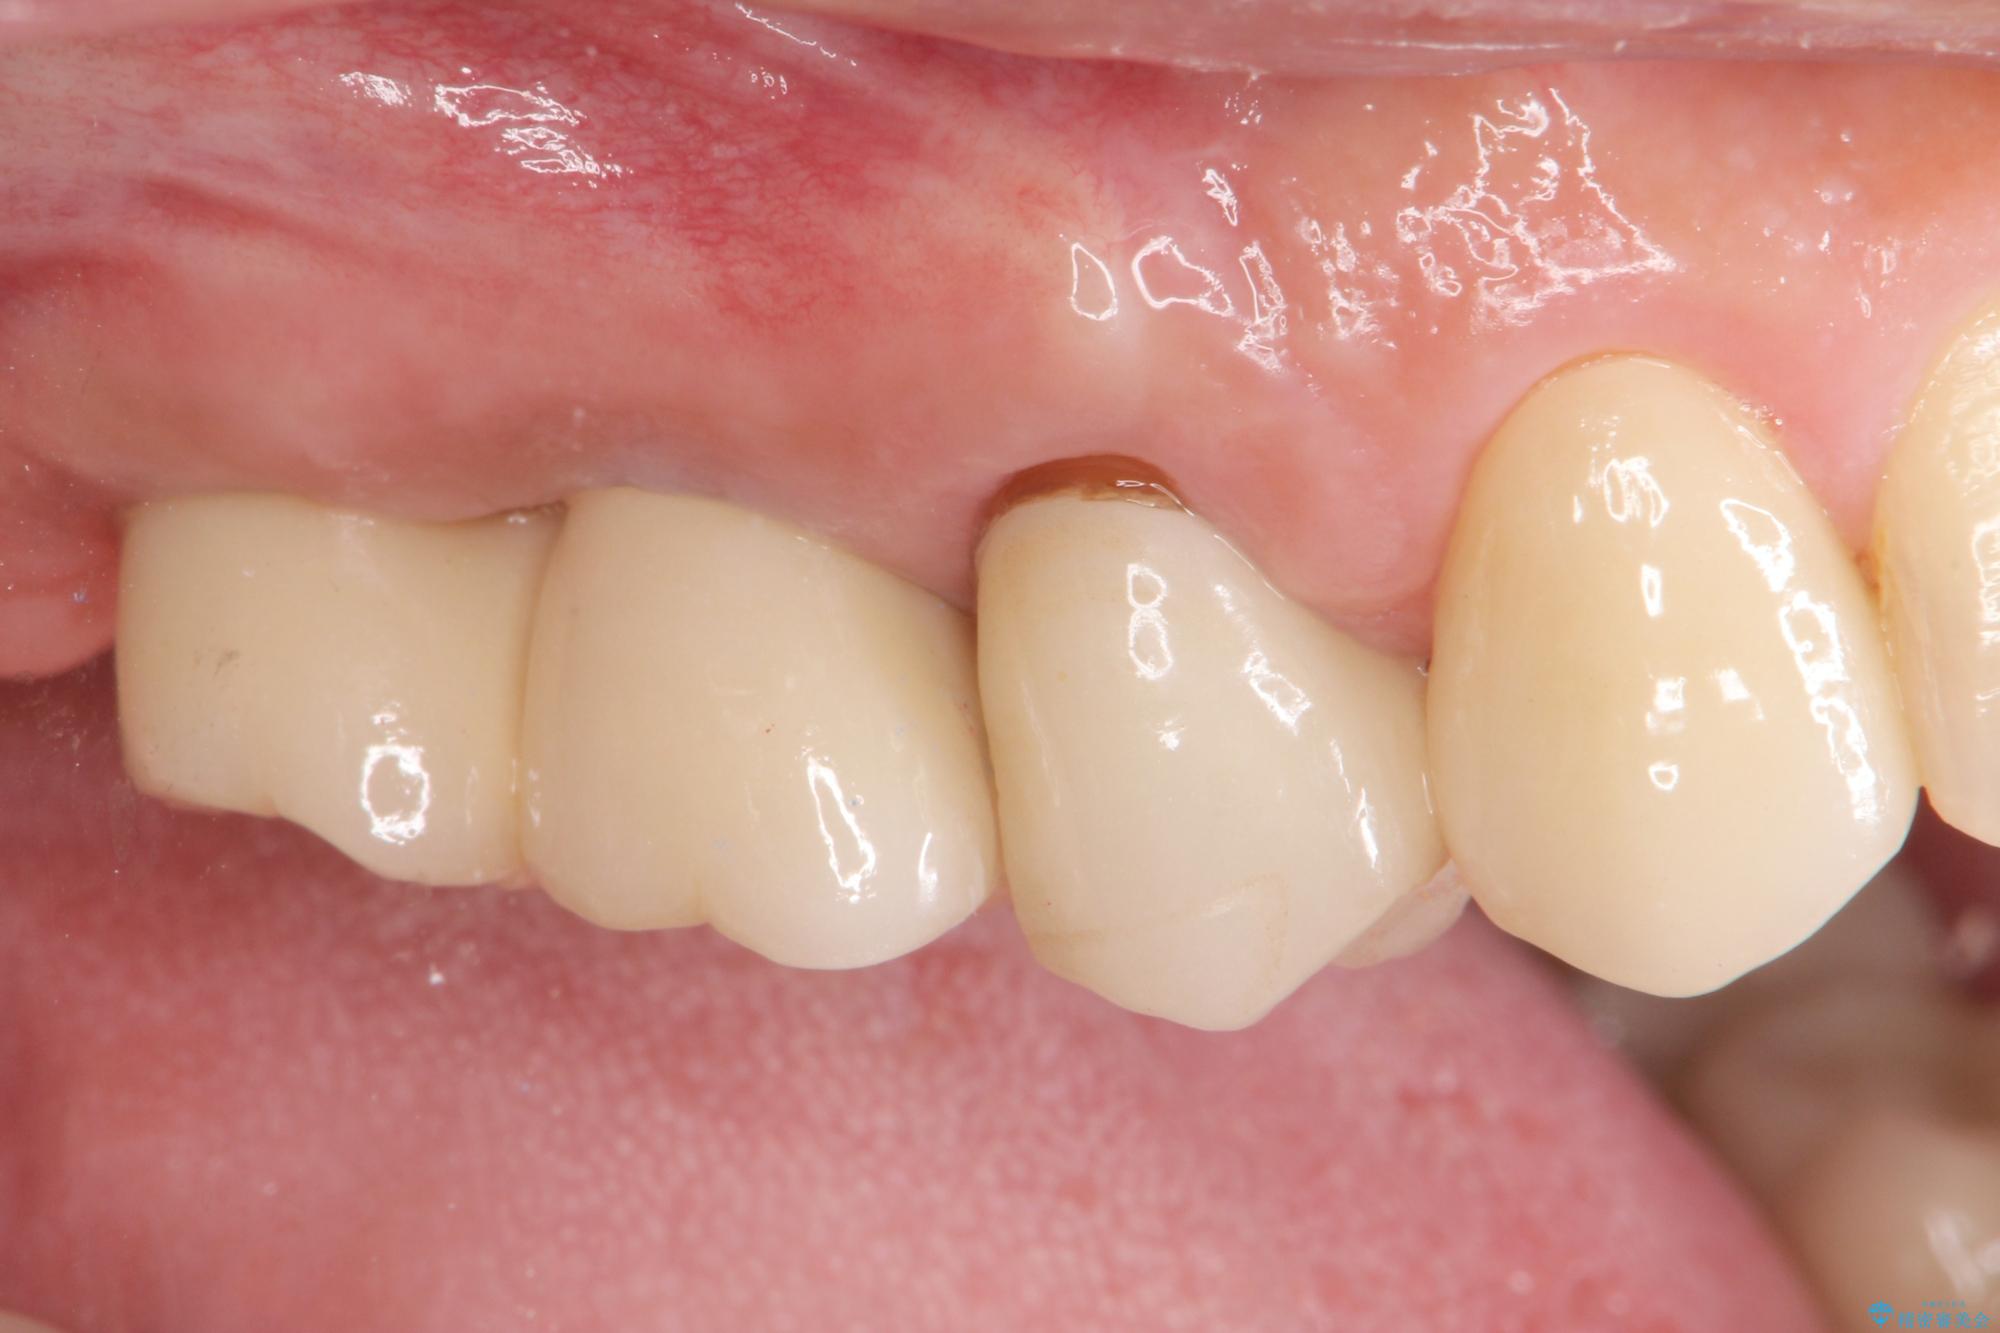

- 歯を抜いたまま放置してしまい、「やはりしっかりと噛めるような状態にしてほしい」とインプラント治療を希望され来院されました。

人工歯根であるインプラントを埋入することで奥歯でまたしっかりと噛める咬合機能を回復します。

- 88万円(インプラント×2・仮歯×2・チタンカスタムアバットメント×2・ジルコニアクラウン×2)費用は治療当時の料金となります

またしっかりと噛めるようになり、食事を楽しめるようになった!と喜んでいただくことができました。